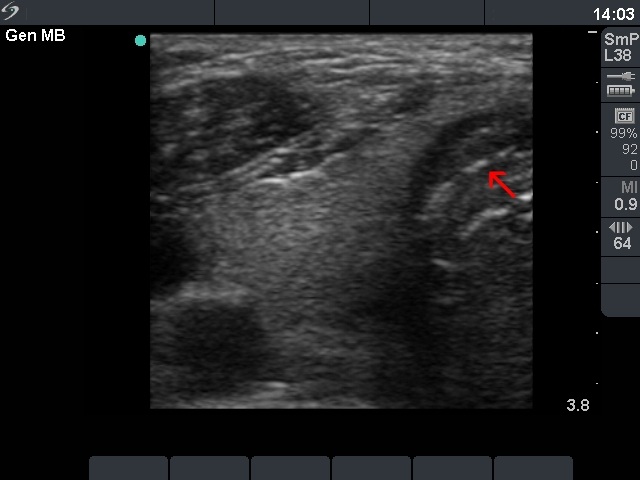

Ultrasonography: the right lobe was intact. On the dorsal part of the left lobe there was hypoechogenic mass spreading to the dorsal part of the isthmus. There was no blood flow within the nodule on color Doppler.

The US pattern is very specific for cancer. Such macroscopic proof of an invasively spreading cancer is rarely seen. The lack of enlarged lymph nodes in the neck would be a very unusual finding in the event of such an aggressive form of a papillary or medullary cancer. This property itself raises the possibility that the thyroid carcinoma is not a primary one.